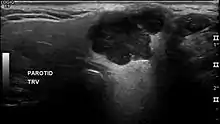

A maioria dos adenomas pleomórficos da glândula parótida ocorrem no lobo superficial e se apresentam como um aumento de volume sobre o ramo da mandíbula à frente da orelha. A dor e a paralisia do nervo facial são raras. Inicialmente, o tumor é móvel, mas torna-se menos móvel com seu crescimento. Se negligenciada, a lesão pode crescer até atingir proporções grotescas. Cerca de 10% dos tumores mistos da parótida desenvolvem-se no lobo profundo da glândula, abaixo do nervo facial. Algumas vezes estas lesões crescem medialmente, entre o ramo ascendente e o ligamento estilomandibular, resultando em um tumor com formato de haltere, que se apresenta como um aumento de volume na parede lateral da faringe ou no palato mole. Em raras ocasiões, os adenomas pleomórficos bilaterais têm sido relatados, desenvolvendo-se num padrão sincrônico ou metacrônico. O palato é a localização mais comum dos tumores mistos de glândula salivar, representando aproximadamente 50% dos exemplos intraorais. Esta localização é seguida pelo lábio superior (27%) e pela mucosa jugal (17%). Os tumores de palato quase sempre são encontrados na região lateral posterior do palato, apresentando-se como um aumento de volume de formato arredondado e de superfície lisa. Se o tumor for traumatizado, uma ulceração secundária pode ocorrer. Devido à natureza forte mente aderida da mucosa do palato duro, os tumores nesta localização não são móveis, embora os da mucosa labial ou da mucosa jugal frequentemente sejam.

O adenoma pleomórfico é um tumor tipicamente encapsulado e bem circunscrito. Entretanto, a cápsula pode ser incompleta ou exibir infiltração por células tumorais. Essa falta de encapsulação completa é mais comum nos tumores de glândula salivar menor, especialmente ao longo da porção superficial dos tumores do palato, abaixo da superfície epitelial.